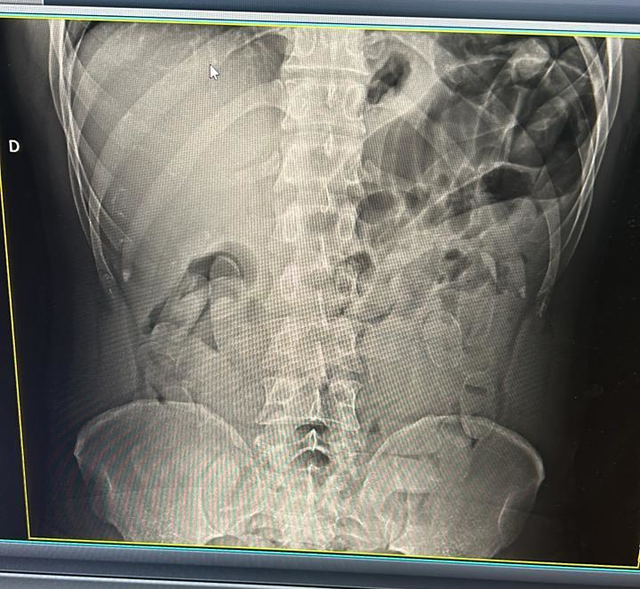

Depois, ele confessou que havia engolido parte do entorpecente. Então, através de raio-X, foi constatado que o boliviano estava com 60 cápsulas da droga no estômago. A operação resultou em prejuízo de quase R$ 140 mil para os criminosos.